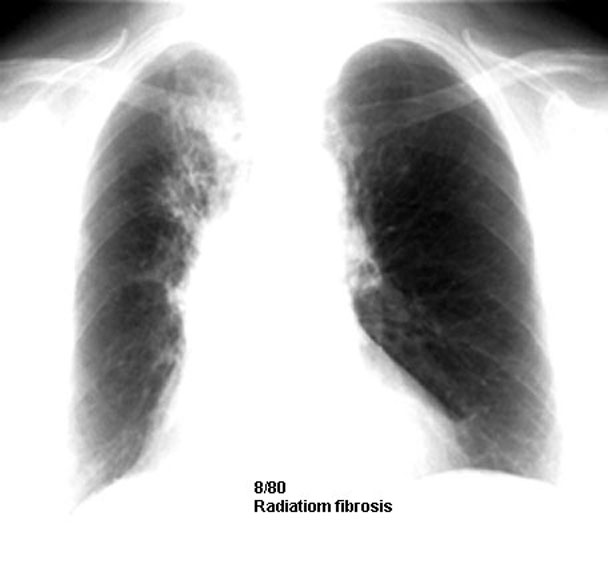

Radiation fibrosis corresponding to radiation port.